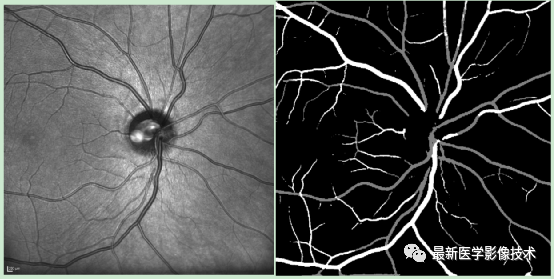

5、测试集部分分割结果